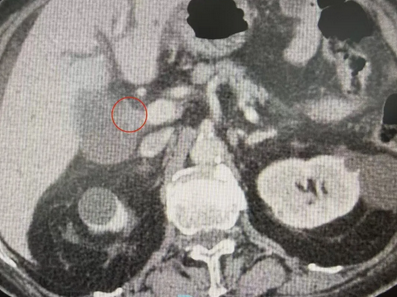

直到半个月前,老人因心脏病发作入住我院心血管内科,准备接受永久性心脏起搏器置入术。然而,术前常规检查时竟查出了“险情”。老人的肝功能指标严重异常,进一步影像学检查提示,肝门部存在占位性病变,高度怀疑是肝门部胆管恶性肿瘤。这一意外诊断让本就棘手的病情雪上加霜,也为后续诊疗出了一道难题。

术前检查时发现肝门部胆管恶性肿瘤